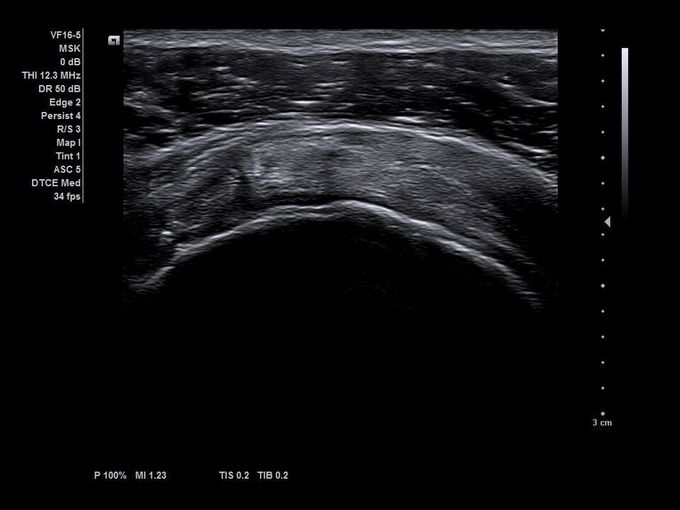

Кроме новой техники, можно заказать восстановленные медицинские системы: ультразвуковые сканеры, томографы, флюороскопы, ангиографы и хирургические установки С-дуга.